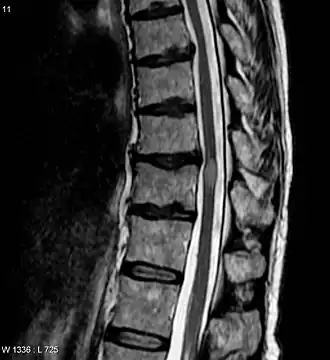

![]() Imagen de resonancia magnética que muestra una lesión de mielitis transversa (ligeramente a la derecha, de forma oval y color más claro). La paciente se recuperó tres meses después. | ||

El diagnóstico se hace a través de la historia clínica, el examen físico, el estudio del líquido cefalorraquídeo (punción lumbar) y, en algunos casos, la resonancia magnética de la médula espinal.